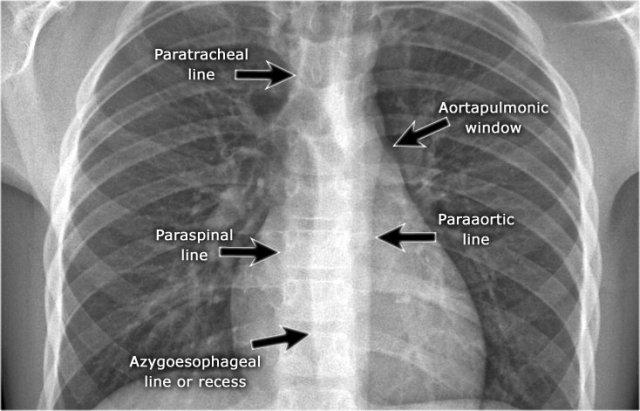

Trên phim X-quang ngực tư thế PA, cần đánh giá cẩn thận tất cả các ranh giới giữa phổi và các cấu trúc lân cận — chẳng hạn như cơ hoành, tim và trung thất.

Tại các ranh giới này, các mặt tiếp giáp giữa phổi và mô mềm tạo thành các hình ảnh có thể nhìn thấy được:

- Các đường hoặc dải (ví dụ: dải cạnh khí quản phải)

- Các bóng mờ viền (ví dụ: cung động mạch chủ hoặc bờ thất trái)

Các đường và bóng mờ viền này đóng vai trò là các mốc giải phẫu và giúp xác định vị trí tổn thương. Khi các đường viền này bị dịch chuyển hoặc bị xóa mờ kèm mất bóng mờ viền bình thường, dấu hiệu bóng mờ viền được xác lập — đây là một đặc điểm chẩn đoán quan trọng.

- Đường cạnh cột sống có thể bị dịch chuyển do áp xe cạnh đốt sống, gãy đốt sống kèm xuất huyết, hoặc u tân sinh lan rộng ra ngoài đốt sống.

- Dày dải cạnh khí quản phải (>2–3 mm) có thể gợi ý hạch to, dày màng phổi, xuất huyết, quá tải dịch hoặc suy tim sung huyết.

- Dịch chuyển đường cạnh động mạch chủ có thể liên quan đến giãn dài động mạch chủ, phình, bóc tách hoặc vỡ động mạch chủ.

Các đường trung thất

Các đường hoặc dải trung thất là ranh giới tiếp xúc giữa mô mềm của các cấu trúc trung thất và nhu mô phổi.

Sự dịch chuyển của các đường này rất có giá trị trong việc phát hiện bệnh lý trung thất, như đã được thảo luận ở trên.

Đường azygô-thực quản

Đường trung thất quan trọng nhất cần tìm kiếm là đường azygô-thực quản, tạo nên ranh giới của ngách azygô-thực quản.

Đường này có thể nhìn thấy trên hầu hết các phim X-quang ngực thẳng.

Các nguyên nhân gây dịch chuyển đường này được tóm tắt trong bảng.